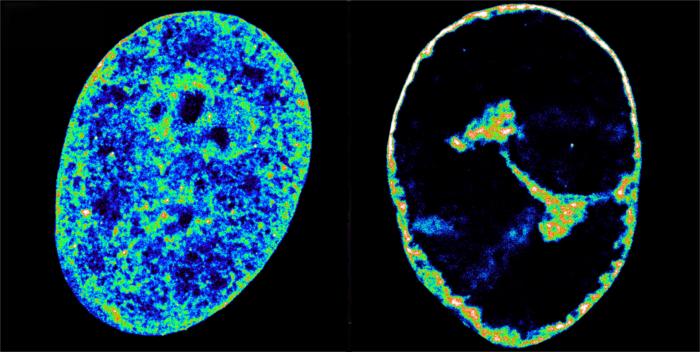

In the study, scientists used super-resolution microscopy to peer into ultra small cell structures just 20 nanometres wide, which is around 3,500 times thinner than a strand of hair.

They combined this with another technique that reveals which bits of DNA are touching inside the nucleus.

These techniques showed that the herpes virus’ hostile takeover begins within the first hour, with the virus hijacking a key human enzyme – RNA-polymerase II – to synthesise its own proteins.

Just three hours after infection, the virus causes a sizeable fraction of molecules involved in human DNA replication to abandon the cell nucleus and enter viral replication compartments.

The wholesale theft causes a collapse of any activity across the host genome, which then gets crushed into a dense shell just 30 per cent of its original volume.